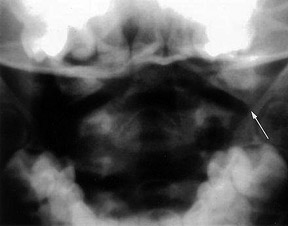

Pseudo subluxation - Copyright – Stock Photo / Register Mark Figure 2: Pseudo subluxation at the C2-3 level; note that the spinolaminar line remains contiguous. Distance Between the Dens and Lateral Masses (Pseudo-Jefferson Fracture): The pseudo-spread of the atlas on the axis (pseudo-Jefferson fracture) is seen on the APOM view. Displacement up to 6 mm of the lateral masses relative to the dens is common up to the age of 4 years old, but can be seen up to 7 years of age. (Figure 1)

Pseudosubluxation at the C2-3 Level: In children, C2 can be displaced anteriorly in relation to C3 and to a lesser extent at the C3-4 level, resembling ligamentous injury. This finding is not uncommon in children less than 8 years of age, but may even be present in 20 percent of children under 16 years of age. It is caused by the horizontal nature of the facets joints in younger ages; as the spine matures the facet joints become more vertical.

True ligamentous injury can be determined by using the posterior cervical line, which is a line drawn from the anterior aspect of the spinous process of C1 to the anterior aspect of the spinous process of C3 (spinolaminar line). The anterior edges of the spinous processes of C1, C2 and C3 should line up within 1 mm of each other on both flexion and extension X-rays. If this line does not overlap the anterior aspect of the spinous process of the C2 by 2 mm or more, a true injury is present. (Figure 2)